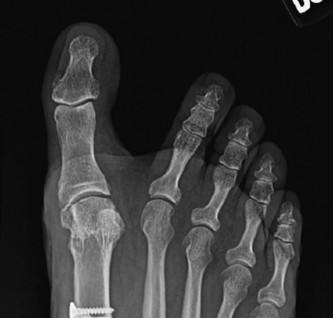

Figure 2: Intraoperative view depicting the medial eminence resection, ensuring the cut is parallel to the metatarsal shaft and avoids the plantar articulation.

Figure 3: Resected medial eminence fragment, demonstrating the size and orientation of the bone removed.

Medial Eminence Resection Bunionectomy

Resection Plane: This is the most critical step for avoiding hallux varus and recurrence.

- The cut should be made parallel to the medial shaft of the first metatarsal, extending distally.

- The resection should remove the prominent bone but not extend into the sagittal groove where the sesamoids articulate plantarly. Over-resection into this groove destabilizes the sesamoids and significantly increases the risk of hallux varus.

- The cut should ideally be just medial to the articular cartilage of the metatarsal head, preserving the cartilage surface.

- Technique: Use an oscillating saw. A common guideline is to resect the medial eminence flush with the medial cortex of the first metatarsal shaft. Visually inspect the joint after resection to ensure no violation of the plantar articular surface.

- Goal: To remove the bony prominence causing pain and shoe wear issues, while preserving the integrity and stability of the first MTP joint.